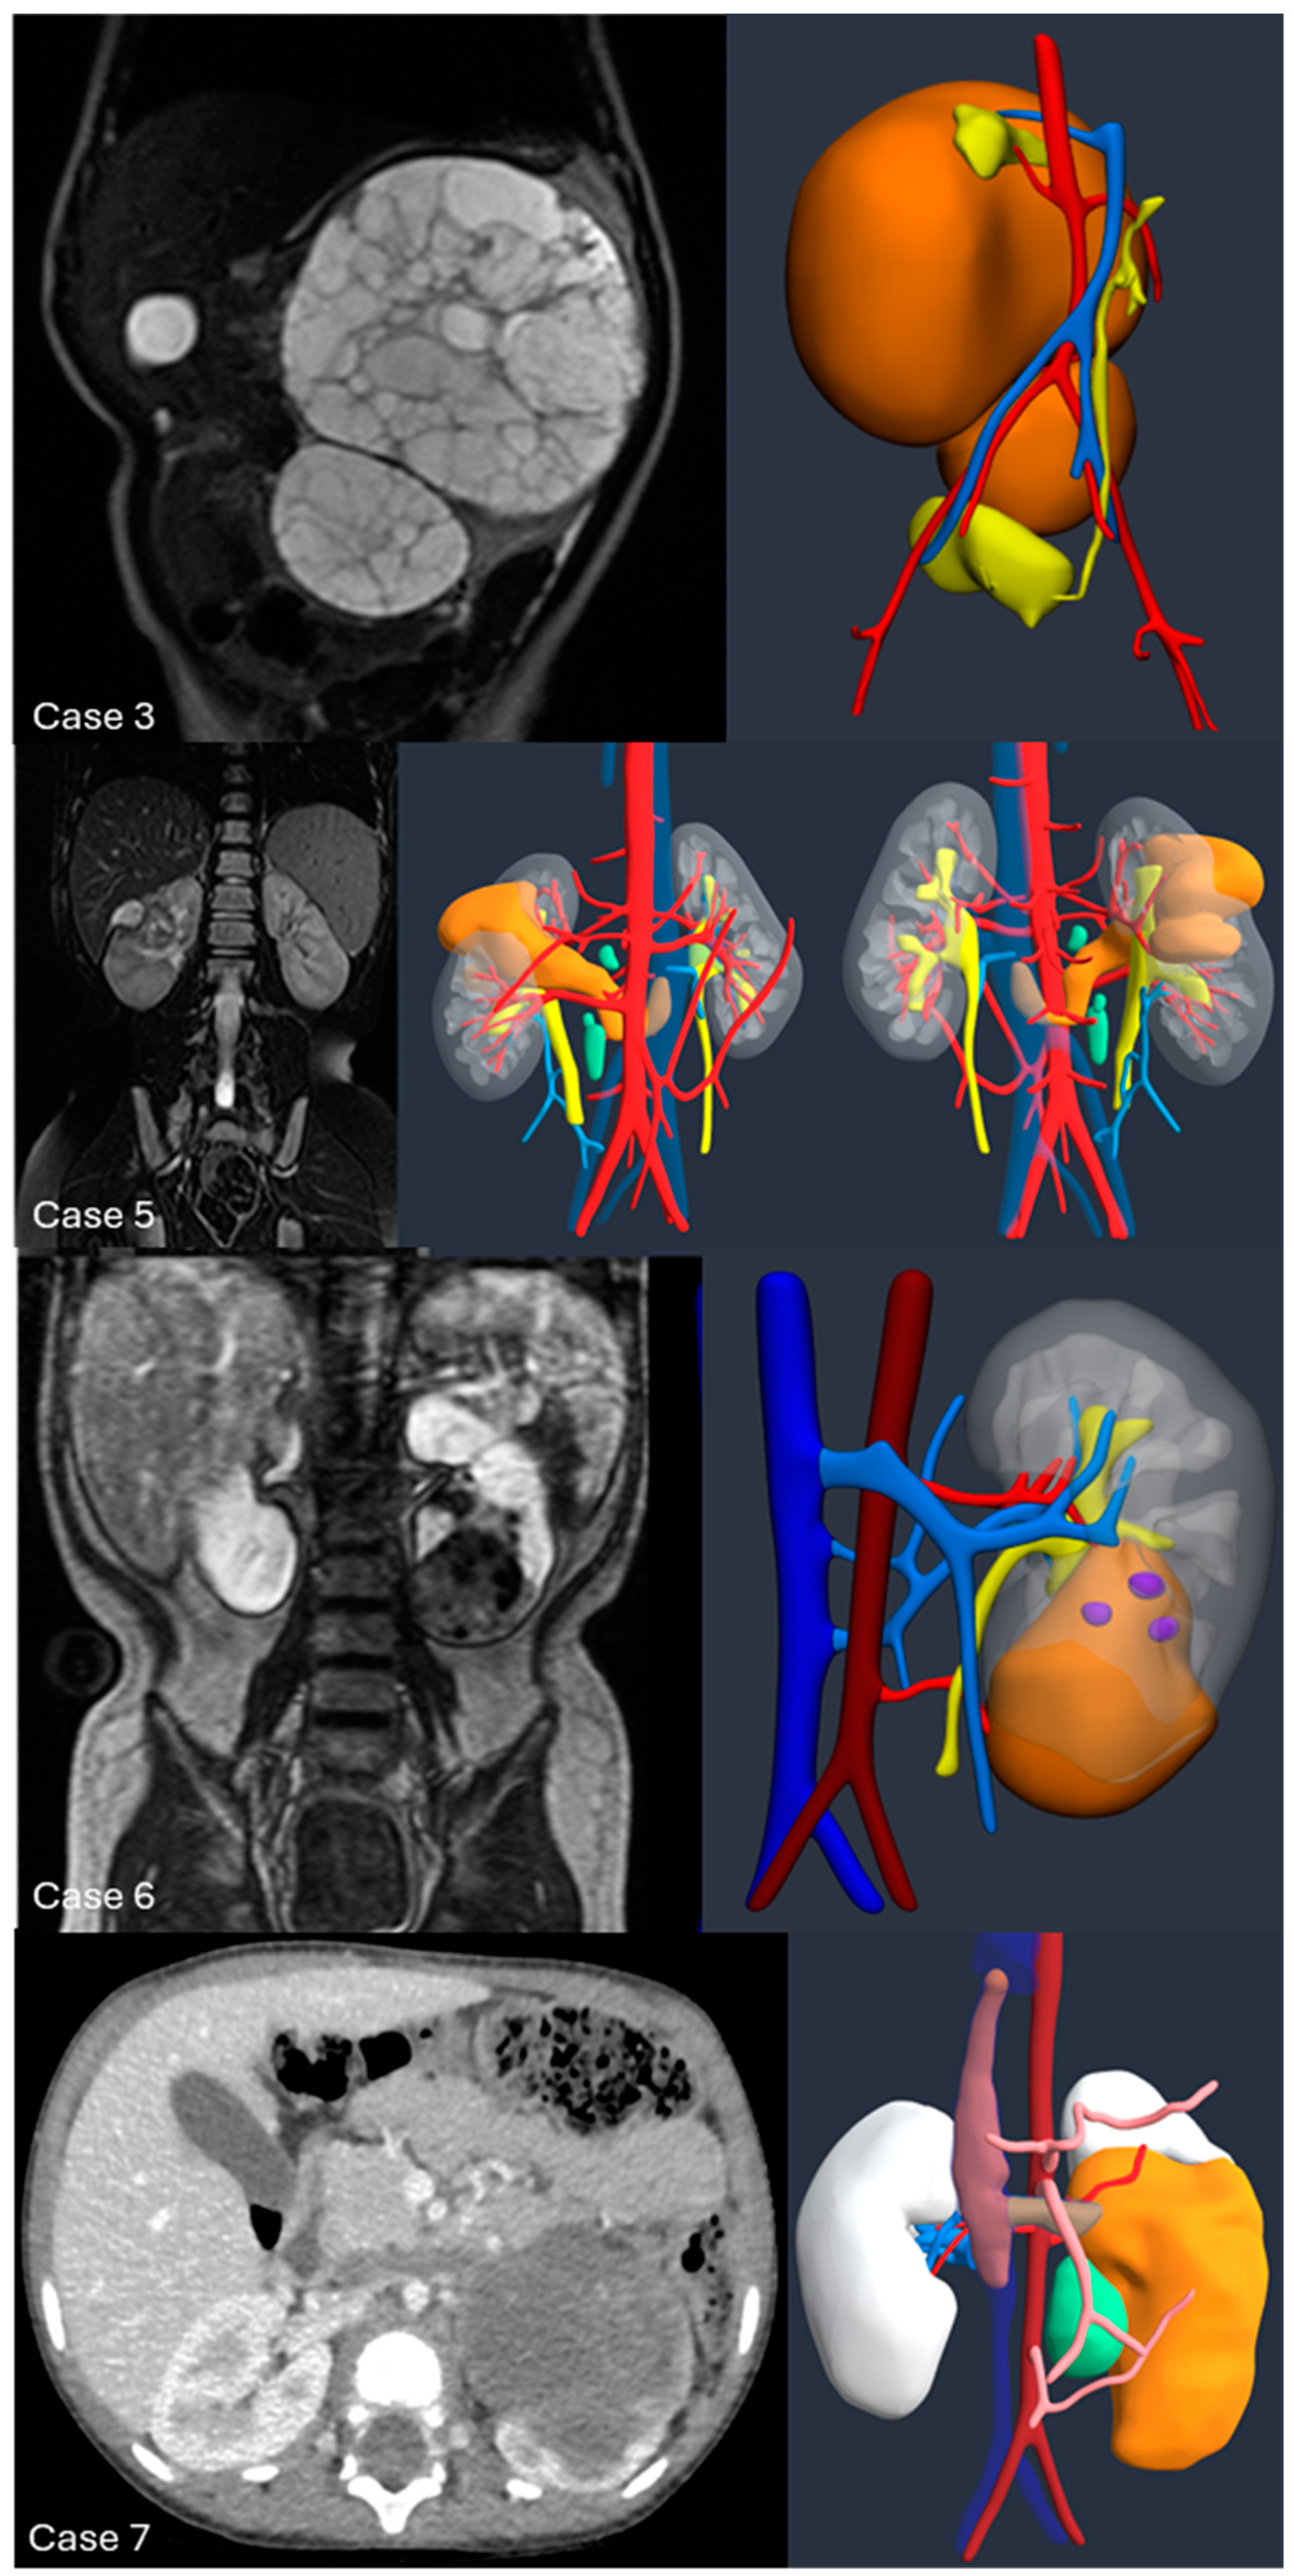

Introduction:The pre-operative planning for complex renal masses in children can be challenging, especially when nephron-sparing surgery (NSS) is recommended. We re-port our experience with the use of 3D-virtual reconstruction (3DVR) and its impact on surgical decision making. Materials and methods: Patients with complex renal masses underwent preoperative 3DVR. DICOM data were obtained from abdominal MRI and/or CT scans. 2D images segmentation was then performed. Three oncology surgeons were asked to individually evaluate each patient's preoperative MRI, CT and 3DVR. A questionnaire regarding the quality of conventional imaging compared to 3DVR was completed following surgery. Results: 8 patients (4♂,4♀) were included: Cases 1,2 and 4 were circumscribed tumours in the right upper pole, left lower pole (Bosniak cyst IV) and right mid-upper pole (Bosniak cyst IIF) respectively; Case 3 was a large hilar mass involving the whole kidney, unresponsive to chemotherapy; Case 5 and 7 were stage IV Wilms' tumour with venous thrombosis; case 6 was a left mid lower renal mass in a patient with WAGR syndrome and acute lymphoblastic leukae-mia (ALL) and case 8 was a recurrent central right WT after previous NSS in a child with Beckwith-Wiedemann syndrome(BWS). Four radical nephrectomies and three NSS were performed. In comparison to conventional imaging, the 3DVR models were judged to be superior by the expert reviewers for all anatomical structures except the urinary tract(p< 0.05). Conclusions: Our study suggests that 3DVR can be considered a useful tool in the pre-operative evaluation of children with complex renal masses and can facilitate NSS in selected patients.

| Case | 1 | 2 | 3 | 4 | 5 | 6 | 7 | 8 |

| Sex (M/F) | F | M | M | M | F | F | M | F |

| Age (months) | 48 | 180 | 14 | 178 | 50 | 42 | 28 | 52 |

| Weight (kg) | 15 | 50 | 9.4 | 70 | 18 | 10.8 | 13 | 17 |

| Side | Right | Left | Left | Right | Right | Left | Left | Right |

| Position | UP | LP | UP+MP+LP | MP+UP | UP | MP+LP | LP | LP |

| Volume (ml) at surgery | 33 | 24 | 597 | 23 | 421 | 63 | 136 | - |

| Syndrome | - | - | - | - | - | WAGR | - | BWS |

| MRI | X | X | X | X | X | X | X | X |

| CT scan | X | X | - | X | X | X | X | X |

| Vein Thrombosis | - | - | - | - | X | - | X | - |

| UCSI | - | - | - | - | - | X | - | - |

| Surgery | RAL NSS | RAL NSS |

Open nephrectomy | RAL NSS | Open Nephrectomy | Open Nephrectomy | Open Nephrectomy | - |

| Operative time (minutes) | 210 | 200 | 240 | 150 | 450 | 310 | 320 | - |

| Histology | WT | TRCC | CN | CN | WT | WT | WT | - |